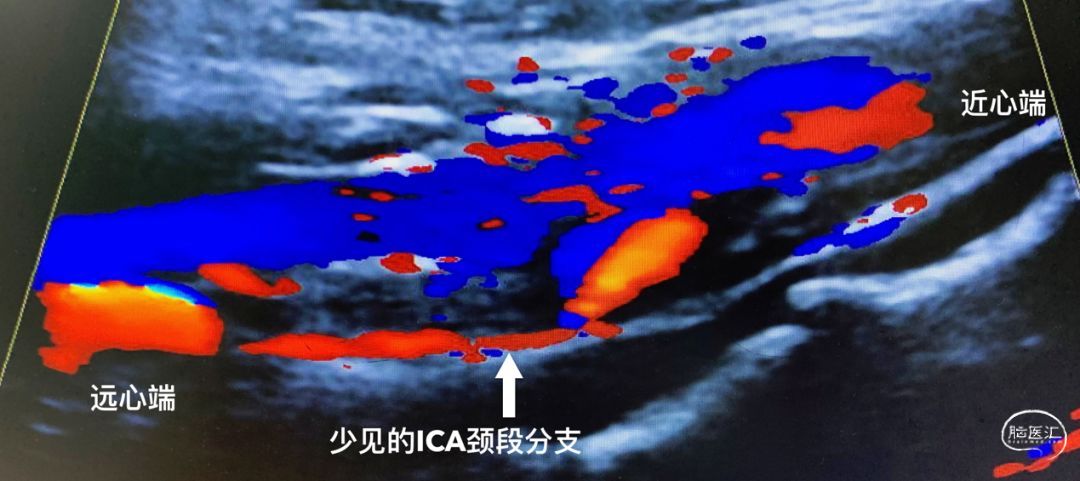

恰好我那天有点空闲,惬意地看同志们忙碌![]() ,随即大家观点一拍即合——急诊复合手术再通。也许是运气好,都是新鲜血栓,返向血流就可以把新鲜血栓推挤出来,随后马上联系手术室,连夜手术!血管超声的美女闻讯而来,弱弱的抛来一句“是闭塞,但闭塞远端通畅,有一支小血管供血”,这是什么道理?ICA颈段的分支?

,随即大家观点一拍即合——急诊复合手术再通。也许是运气好,都是新鲜血栓,返向血流就可以把新鲜血栓推挤出来,随后马上联系手术室,连夜手术!血管超声的美女闻讯而来,弱弱的抛来一句“是闭塞,但闭塞远端通畅,有一支小血管供血”,这是什么道理?ICA颈段的分支?

第一个病例,是少见的咽升动脉异常起源,但在变异中还是相对常见一点。胚胎发育过程中,ICA的颈段来自第三主动脉弓,异常咽升动脉可以看作是第三主动脉弓背侧的残留。对于患者,也许这是一支救命的变异血管,但对于术者则有点尴尬,因为无法阻断,术中是会不断流血的,只能尽快缝合,对此,还有医生专门撰文总结。